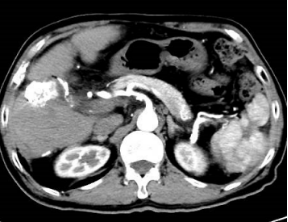

2021年4月肝脏CT增强提示肿瘤明显增大,侵犯胆囊

2022年11月CT增强提示肿瘤无活性